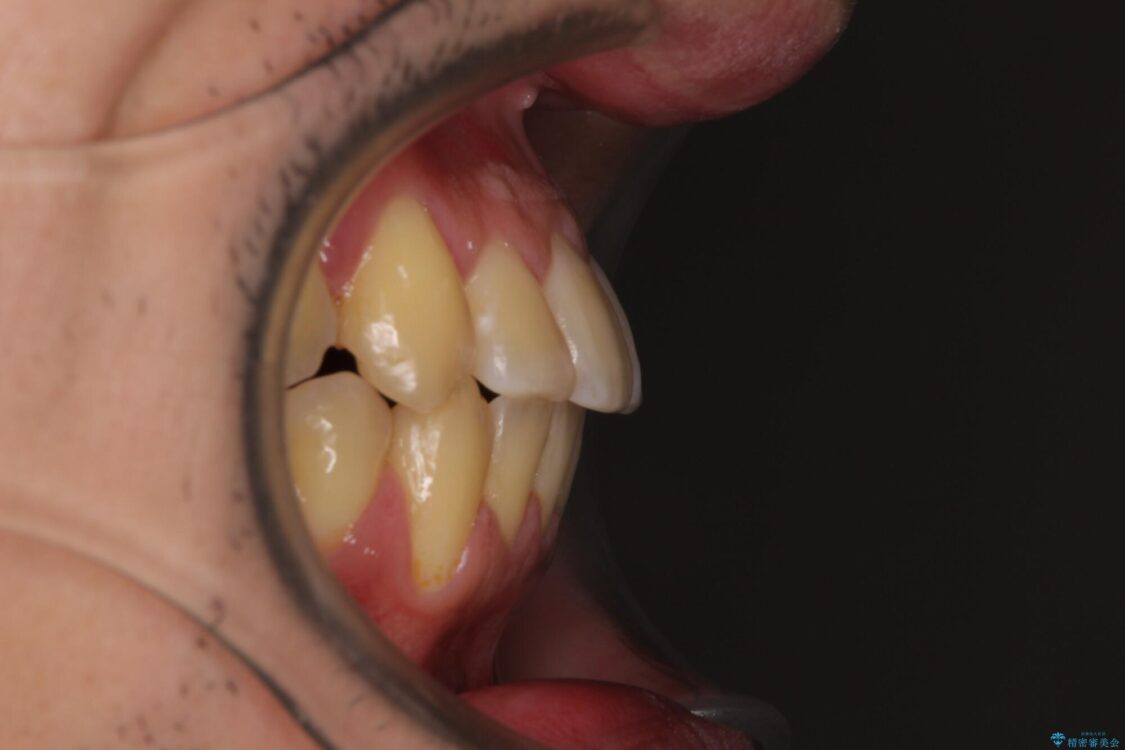

八重歯と前歯のクロスバイトを改善したいとのことで来院された患者様です。

デコボコの程度は強かったのですが、口元の突出感はなかったため、非抜歯矯正としました。

治療前

• 八重歯とクロスバイト 目立たないワイヤー装置で矯正治療 治療前画像